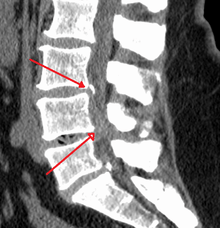

The diagnosis of spinal stenosis involves a complete evaluation of the spine. The process usually begins with a medical history and physical examination. X-ray and MRI scans are typically used to determine the extent and location of the nerve compression.

CT myelogram

A spinal tap is performed in the low back with dye injected into the spinal fluid. X-Rays are performed followed by a CT scan of the spine to help see narrowing of the spinal canal. This is a very effective study in cases of lateral recess stenosis. It is also necessary for patients in which MRI is contraindicated, such as those with implanted pacemakers.